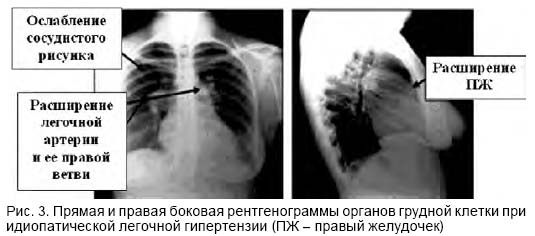

- рентгенография легких позволяет оценить состояние артерии, ее расширение и сужение;